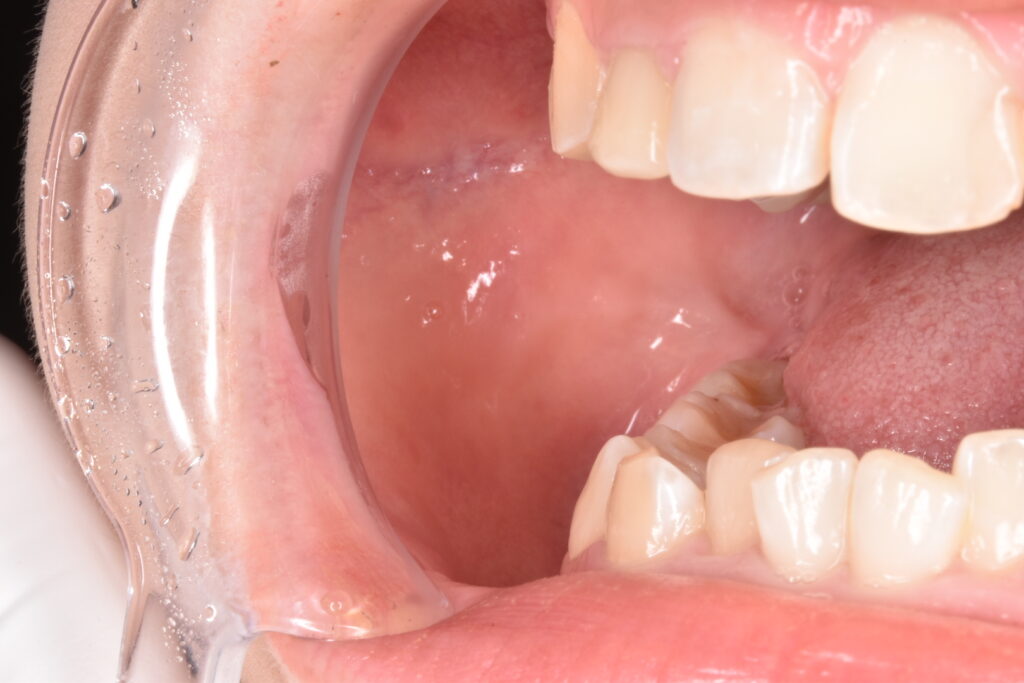

バッカルファット除去前

お顔だけでなく、口腔内の診察、歯列の関係性、頭蓋骨や下顎骨の関係性を審査します。